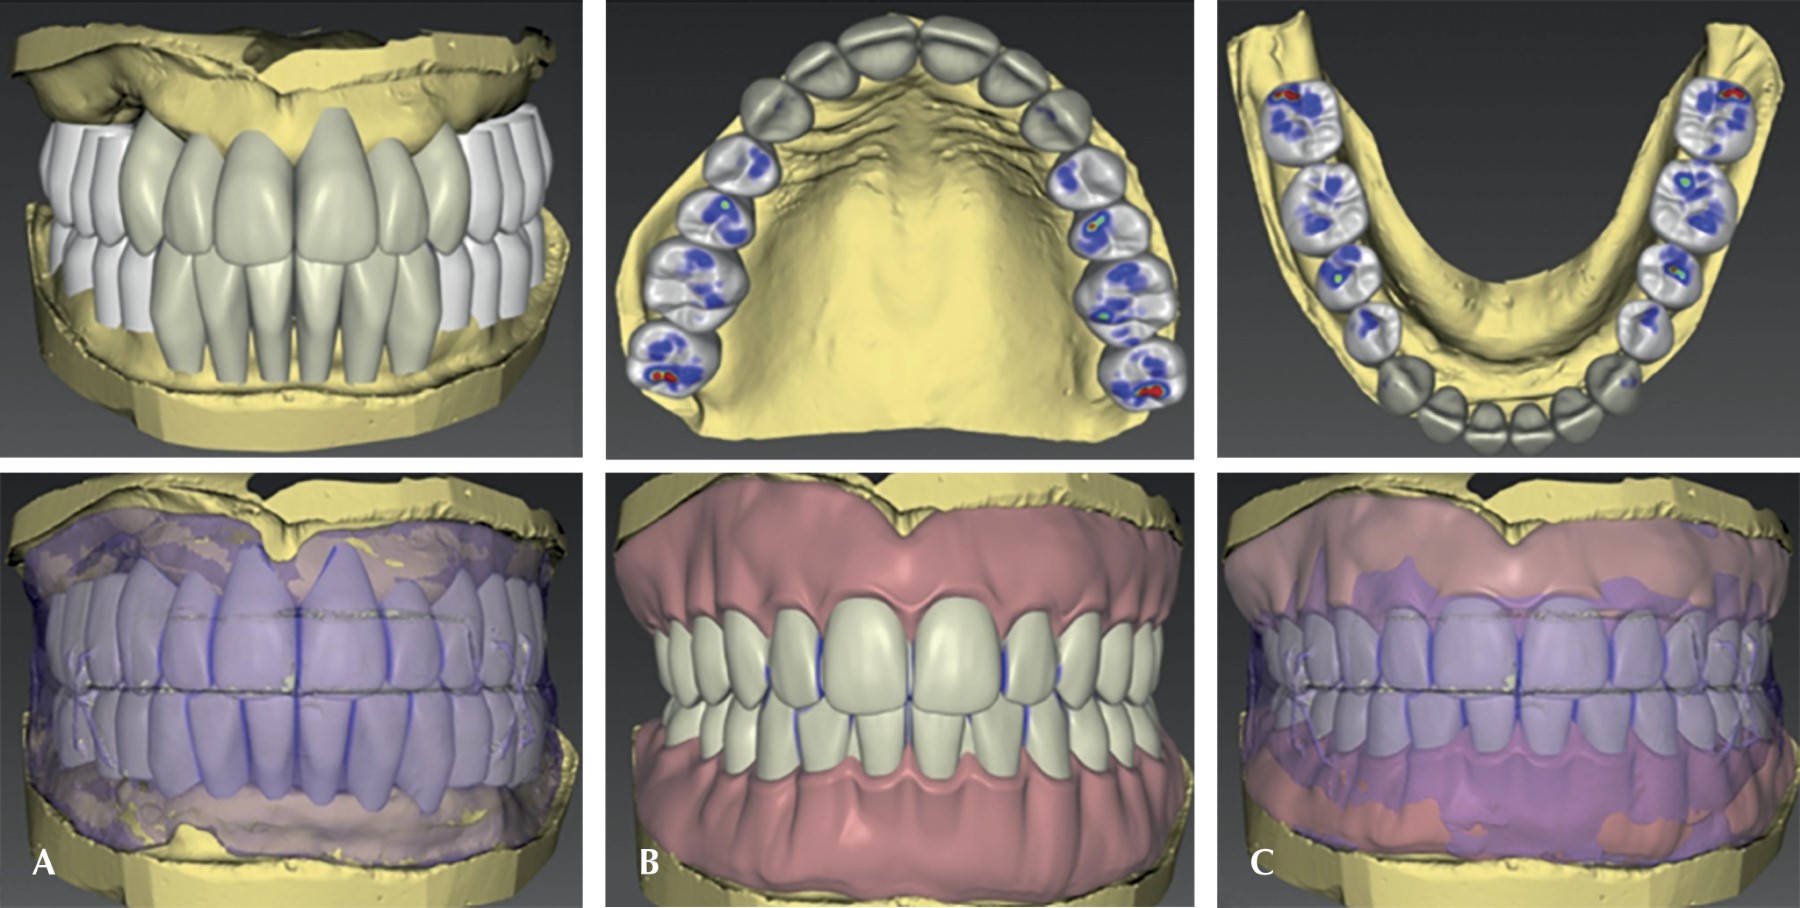

Las prótesis inmediatas fueron realizadas utilizando inLab CAD Software de Dentsply Sirona® en el laboratorio dental de la Universidad de Monterrey. Se tomaron ambos modelos y se procedió a escanearlos, al igual que al registro de mordida. Posteriormente, se comprobó la oclusión y se definió el eje de inserción de las prótesis removibles provisionales; de igual manera, la extensión de la línea base de las prótesis, y se editaron los puntos de referencia anatómicos. El software lanzó un estimado sobre la colocación de las piezas dentales y, posteriormente, se realizaron ajustes en la posición dental (Figura 2). La paciente tenía mordida clase II y se decidió mantenerla en clase II compensada (esto se logró inclinando los OD anterosuperiores hacia lingual e inclinando los anteroinferiores). Una vez que se realizaron las modificaciones en las piezas dentales, estos mismos se compararon con las referencias de los rodillos previamente tomados para que se tuviera la seguridad de la estética y que pudiera desempeñar una correcta función (Figura 2). Por último, se procedió a editar la base de la prótesis y se realizaron ajustes basándonos en las líneas de referencias de máxima sonrisa de los rodillos (Figura 2).